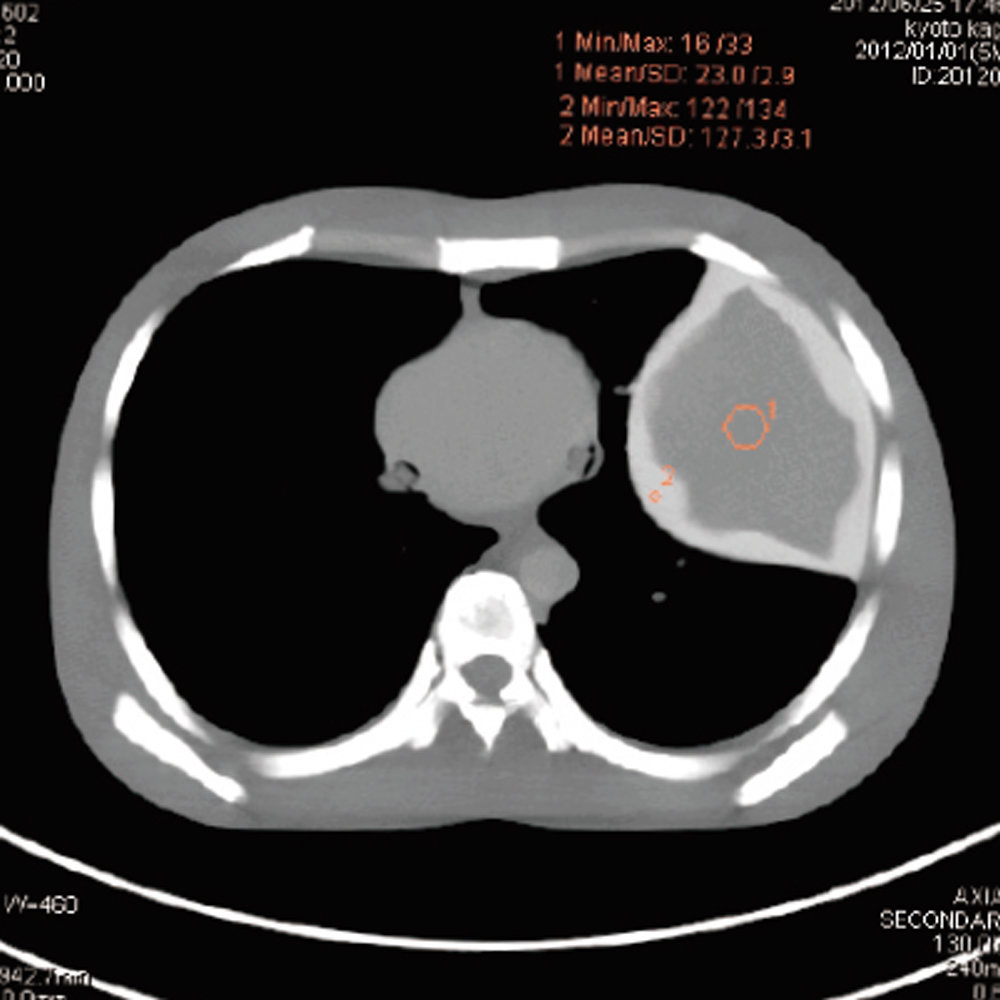

CT Whole Body Phantom - With Pathologies

1A unique, life size whole body phantom for CT provides a variety of educational application as well as visual evaluation in finding out optimal scanning conditions

| Features | 1.Radiology absorption and HU number approximate to human body 2. Main joints have close-to human articulation 3. Phantom can be disassembled into 10 individual parts |

| Training skills / Applications | Plain X-ray / CT /Basic patient positioning |

| Case / Pathology | Refer to PDF( Anatomy and Pathologies) |